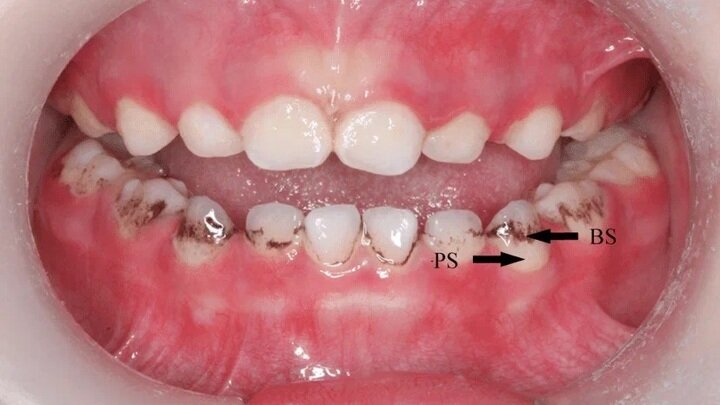

На текущий момент основным источником проблем с зубами считается бактерия Streptococcus mutans, которая активно питается углеводами. Она выделяет кислоты, разрушающие эмаль, что приводит к проникновению в глубь зуба и, в конечном итоге, к болевым ощущениям. Жизнь с кариесом может быть крайне опасной, поскольку стрептококки могут попадать в кровь и вызывать воспаление различных органов. Воспалительный процесс в деснах, особенно при ослаблении иммунной системы, может повлечь за собой серьезные осложнения, такие как гайморит, отит или даже рак горла, что подтверждается исследованиями.